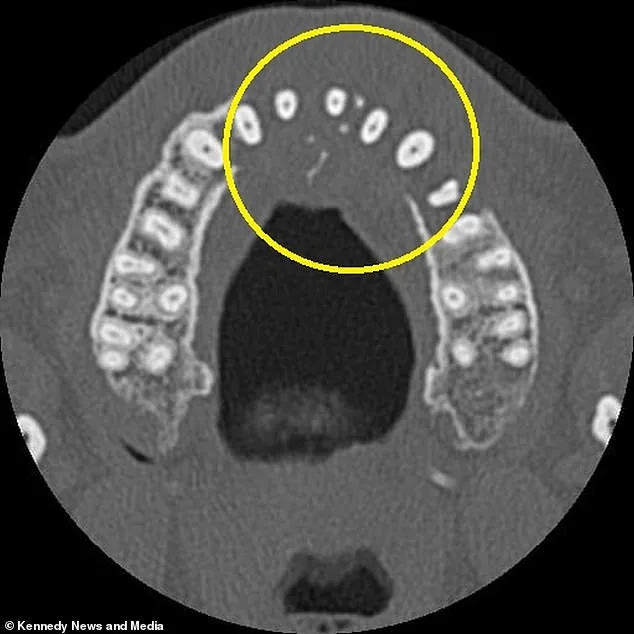

A local dentist in Portugal, where dental care was more affordable than in the UK, performed a routine X-ray that revealed a startling absence of bone on the left side of his upper jaw. This prompted further imaging, including a CT scan, which uncovered a mass growing in his sinus cavity and spreading under his nose. Upon returning to the UK, additional tests confirmed the diagnosis: stage two diffuse large B-cell lymphoma (DLBCL), a fast-growing type of non-Hodgkin lymphoma that affects white blood cells. X-rays showed the tumor had 'eaten' through his upper jawbone, and the cancer had already begun to spread to his neck.